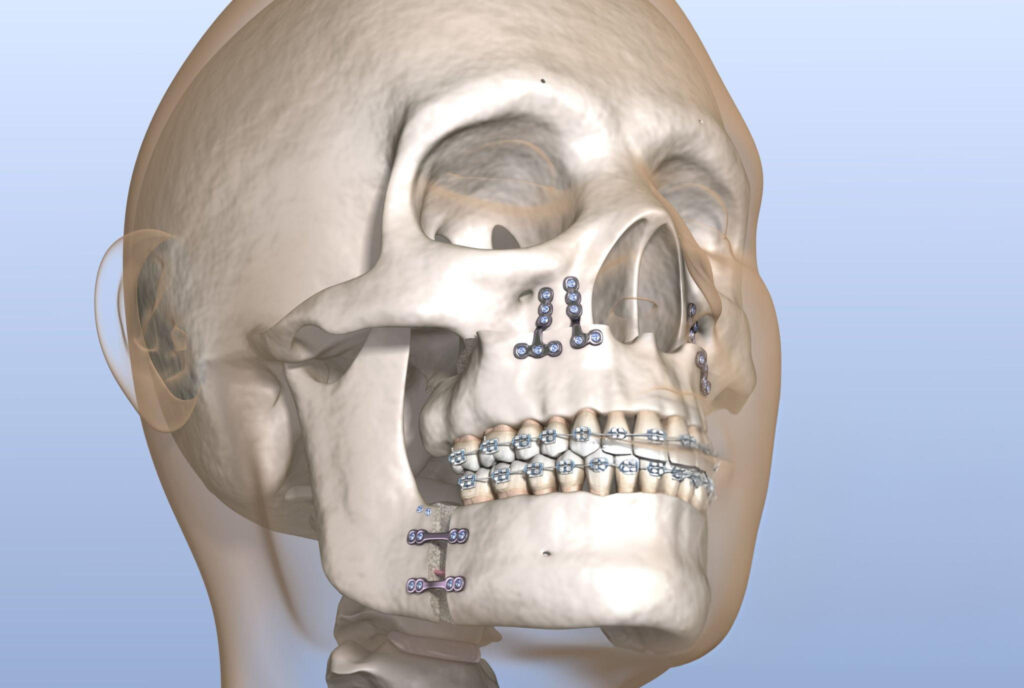

Corrective jaw surgery, also known as orthognathic surgery, is a specialized procedure designed to address irregularities in the jaw bones and realign the jaws and teeth to improve their function. This surgery can be recommended for individuals experiencing difficulties with chewing, speech, breathing, or facial symmetry due to skeletal misalignment. At Ibdaa Dental Clinic, our professional surgeons utilize advanced 3D imaging and precise digital planning to deliver personalized treatments that not only enhance your oral health, but also boost your confidence and facial aesthetics.

Your journey begins with an in-depth consultation and detailed diagnostics, including x-rays and digital scans to assess your jaw structure. The surgical procedure is carried out under general anesthesia and involves repositioning the jaw bones for optimal alignment. Recovery involves a gradual process; most patients resume everyday activities within a few weeks. Throughout your healing process, our team provides continuous support and post-surgery guidance to ensure your comfort, safety, and the best possible results.